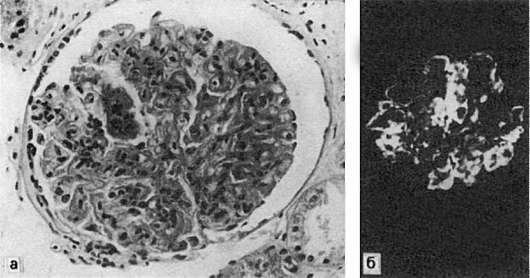

Рис.

79. Реакция гиперчувствительности немедленного типа:

а - острое иммунное воспаление: участки фибриноидного набухания и фибриноидного некроза капилляров почечного клубочка при волчаночном гломерулонефрите; б - в участках фибриноида фиксация IgG (иммунолюминесцентное исследование)